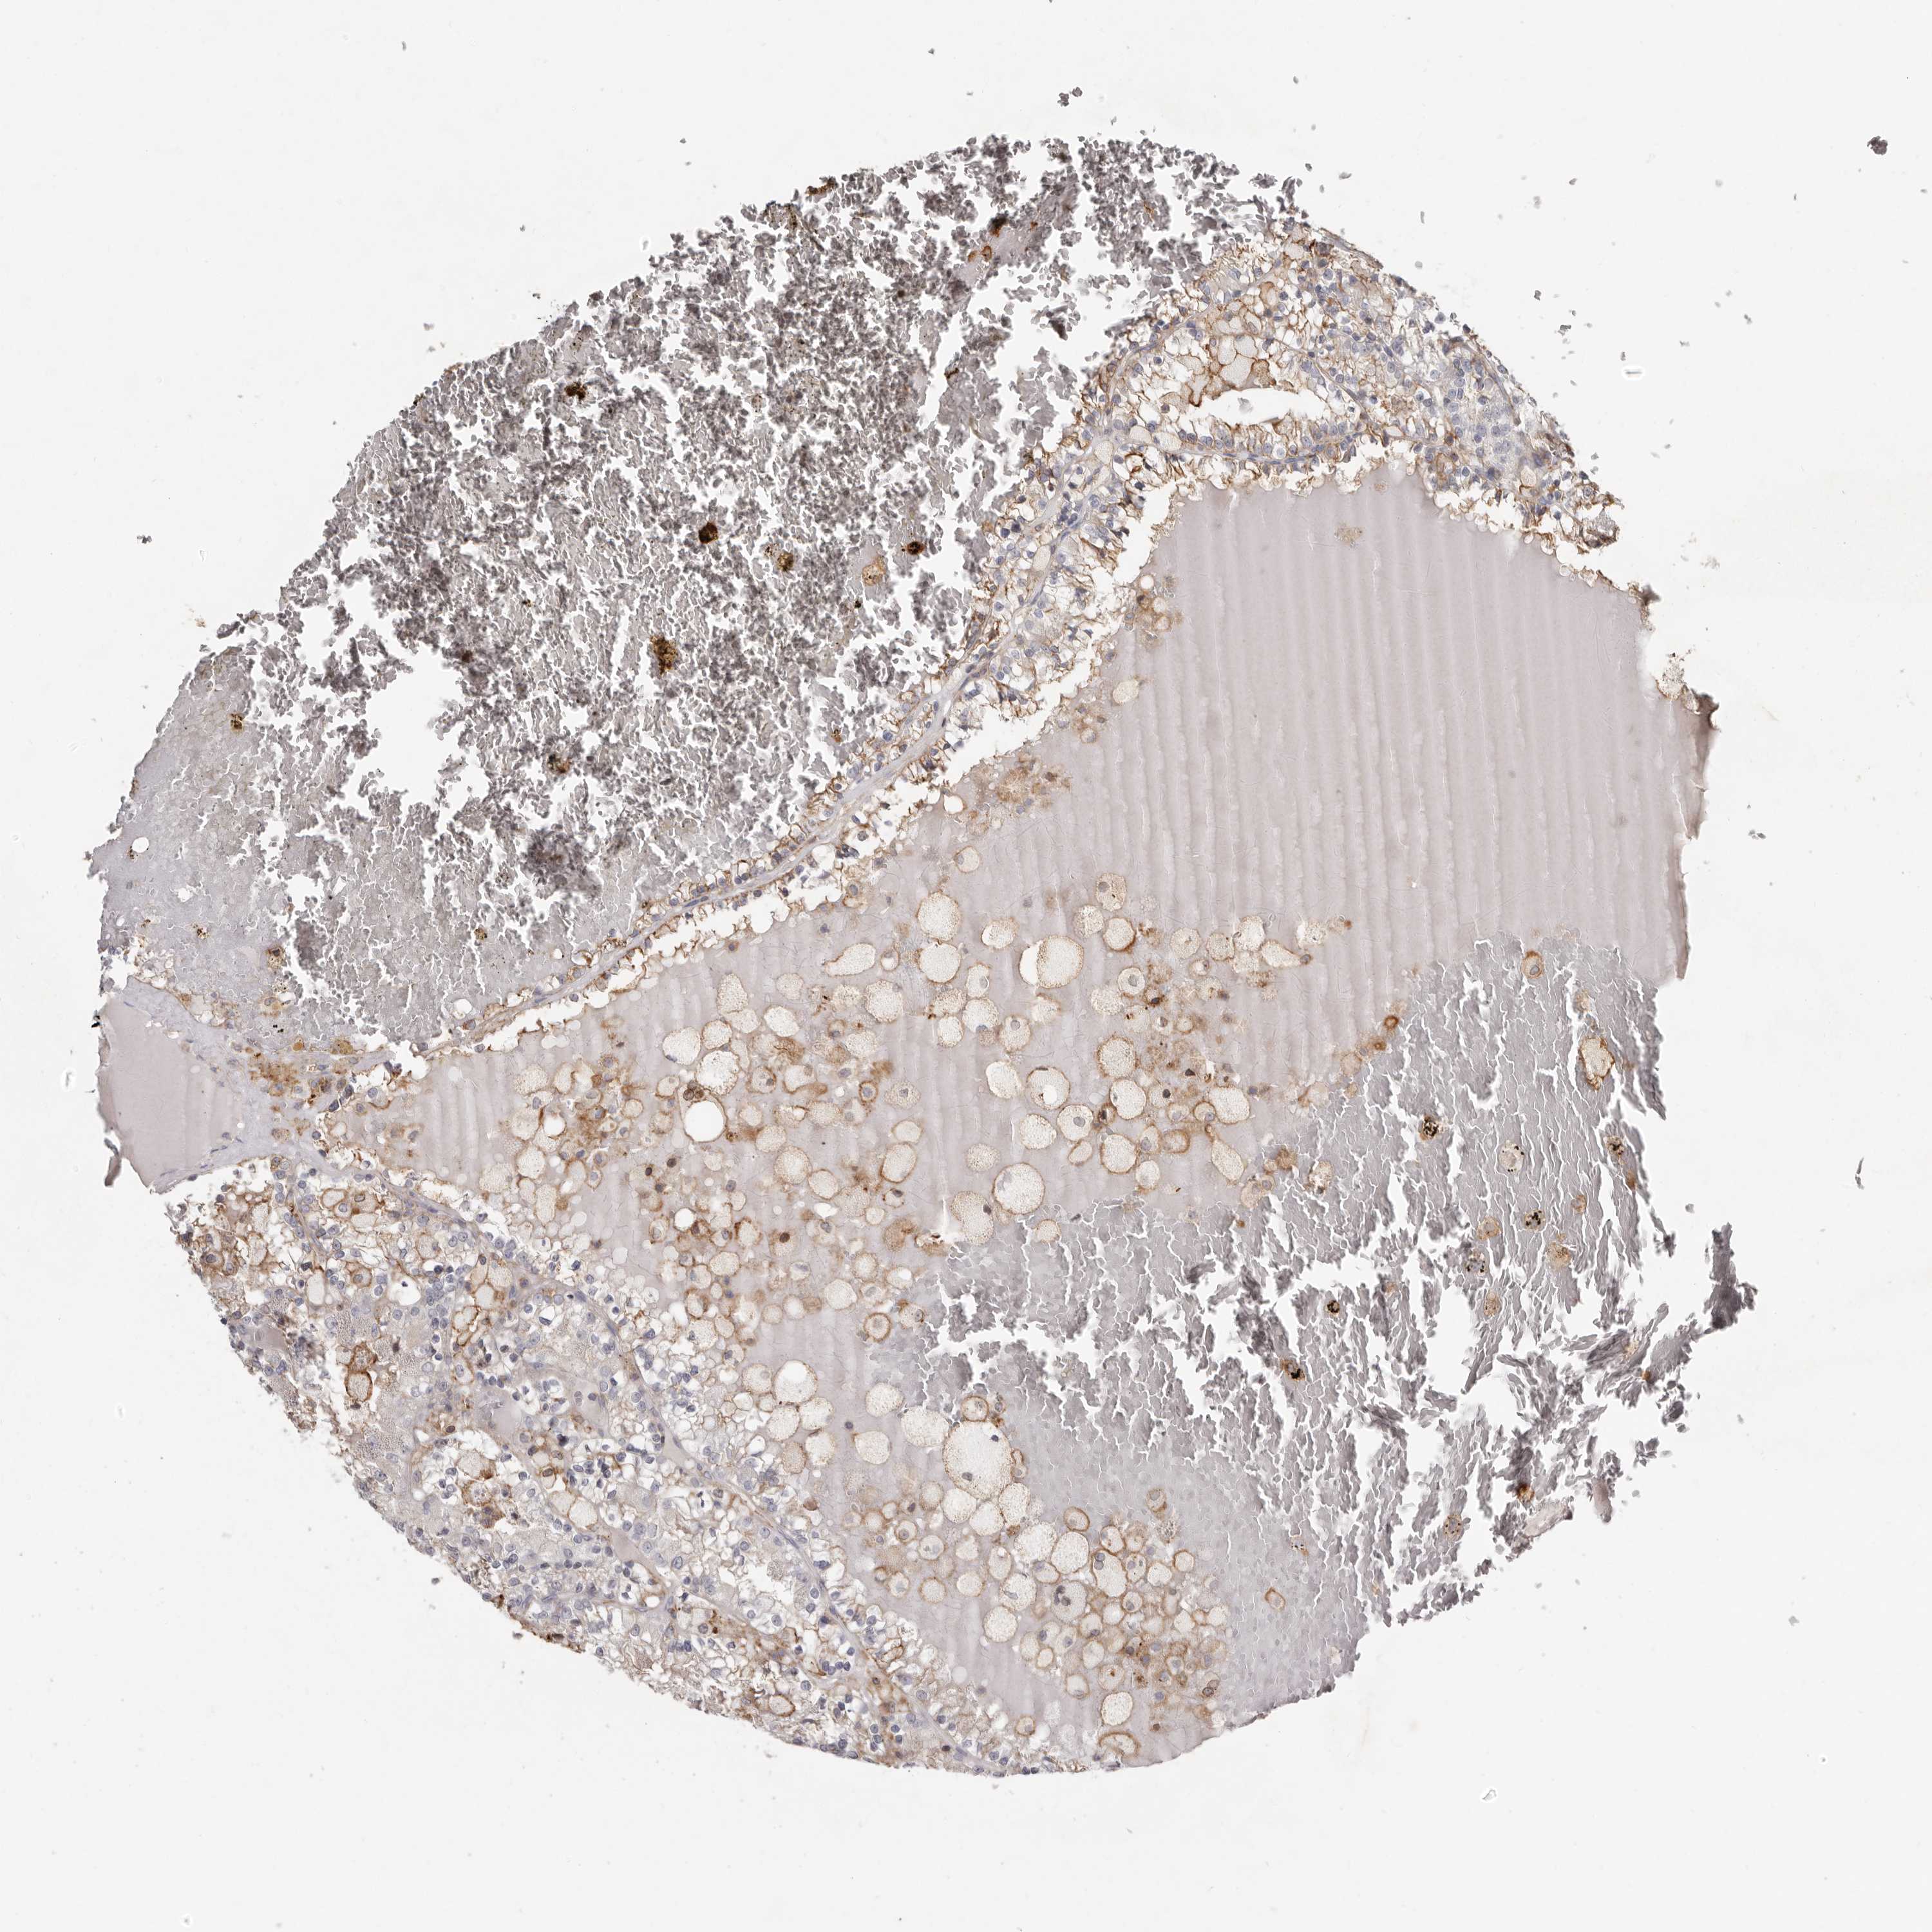

KIDNEY RENAL PAPILLARY CELL CARCINOMA (TCGA) - Interactive survival scatter ploti

The Survival Scatter plot shows the clinical status (i.e. dead or alive) for all individuals in the patient cohort, based on the same data that underlies the corresponding Kaplan-Meier plots. Patients that are alive at last time for follow-up are shown in blue and patients who have died during the study are shown in red.

The x-axis shows the expression levels (FPKM) of the investigated gene in the tumor tissue at the time of diagnosis. The y-axis shows the follow-up time after diagnosis (years). Both axes are complimented with kernel density curves demonstrating the data density over the axes. The top density plot shows the expression levels (FPKM) distribution among dead (red) and alive patients (blue). The right density plot shows the data density of the survived years of dead patients with high and low expression levels respectively, stratified using the cutoff indicated by the vertical dashed line through the Survival Scatter plot. This cutoff is automatically defined based on the FPKM cutoff that minimizes the p-score. The cutoff can be changed by dragging the vertical line or by entering a cutoff value in the square labeled "Current cut-off".

Under the Survival Scatter plot the p-score landscape (black curve; left axis) is shown together with dead median separation (red curve; right axis). Dead median separation is the difference in median mRNA expression between patients who have died with high and low expression, respectively. It is calculated as follows: median FPKM expression of dead patients with high expression - median FPKM expression of dead patients with low expression. This is intended to aid the user in visually exploring custom cutoffs and the associated p-scores and dead median separation.

Individual patient data is displayed and can be filtered by clicking on one or more of the category buttons on the top of the page. Categories describing expression level and patient information include: high, low, alive, dead, female, male and tumor stages. The scale of the x-axis can be toggled between linear and log-scale by clicking on the "x log" button. Mouse-over function shows TCGA ID, patient information and mRNA expression (FPKM) for each patient.

& Survival analysisi

Kaplan-Meier plots summarize results from analysis of correlation between mRNA expression level and patient survival. Patients were divided based on level of expression into one of the two groups "low" (under cut off) or "high" (over cut off). X-axis shows time for survival (years) and y-axis shows the probability of survival, where 1.0 corresponds to 100 percent.

KIF26B is not prognostic in Kidney Renal Papillary Cell Carcinoma (TCGA)